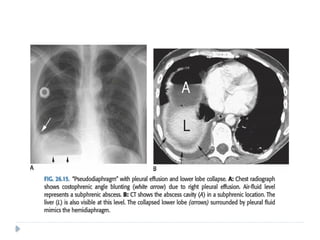

 Subpulmonic effusion.

 These are pleural effusions that can be seen only on a erect projection .

 The pleural fluid lies almost exclusively between the lung base and

diaphragm .

 Radiographs show elevation of the hemidiaphragm.

 What appears to be the diaphragm actually represents the visceral

pleura and the true diaphragm is obscured.

 When the Subpulmonic effusion is left-sided, the distance between the

inferior surface of the left lung and the gastric bubble measures more

than 2 cm.